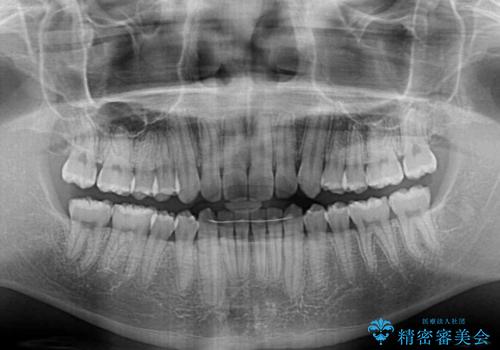

口元を引っ込めるためのゴムかけを頑張っていただき、満足のいく上顎前歯の傾斜へ改善することができました。